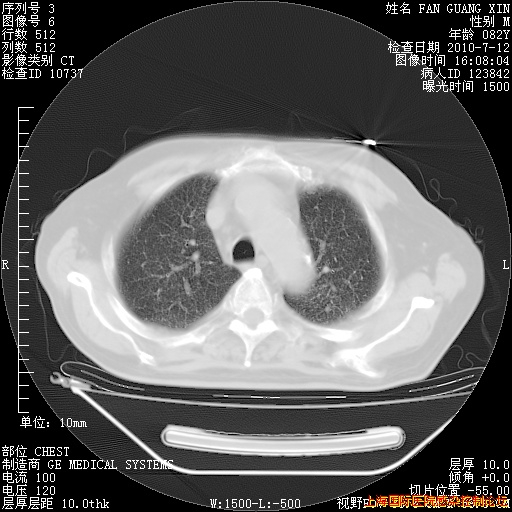

补发6月12日肺部CT肺窗

6月12日肺窗

今天复查CT

今天CT

整整相隔30天的肺部CT好像有所好转啊。甲强龙减量第3天,需要观察体温。

海管,自昨日你和我通完话后,不知您岳父消化道症状有无缓解?体温怎样?阅读7.12日胸部ct,个人认为目前激素治疗是有效的,甲强龙减量是适宜的。因在抗痨治疗,需密切观察肝功、肾功能和血常规。不过,老年、长期住院和大量使用激素,很担心菌群失调发生